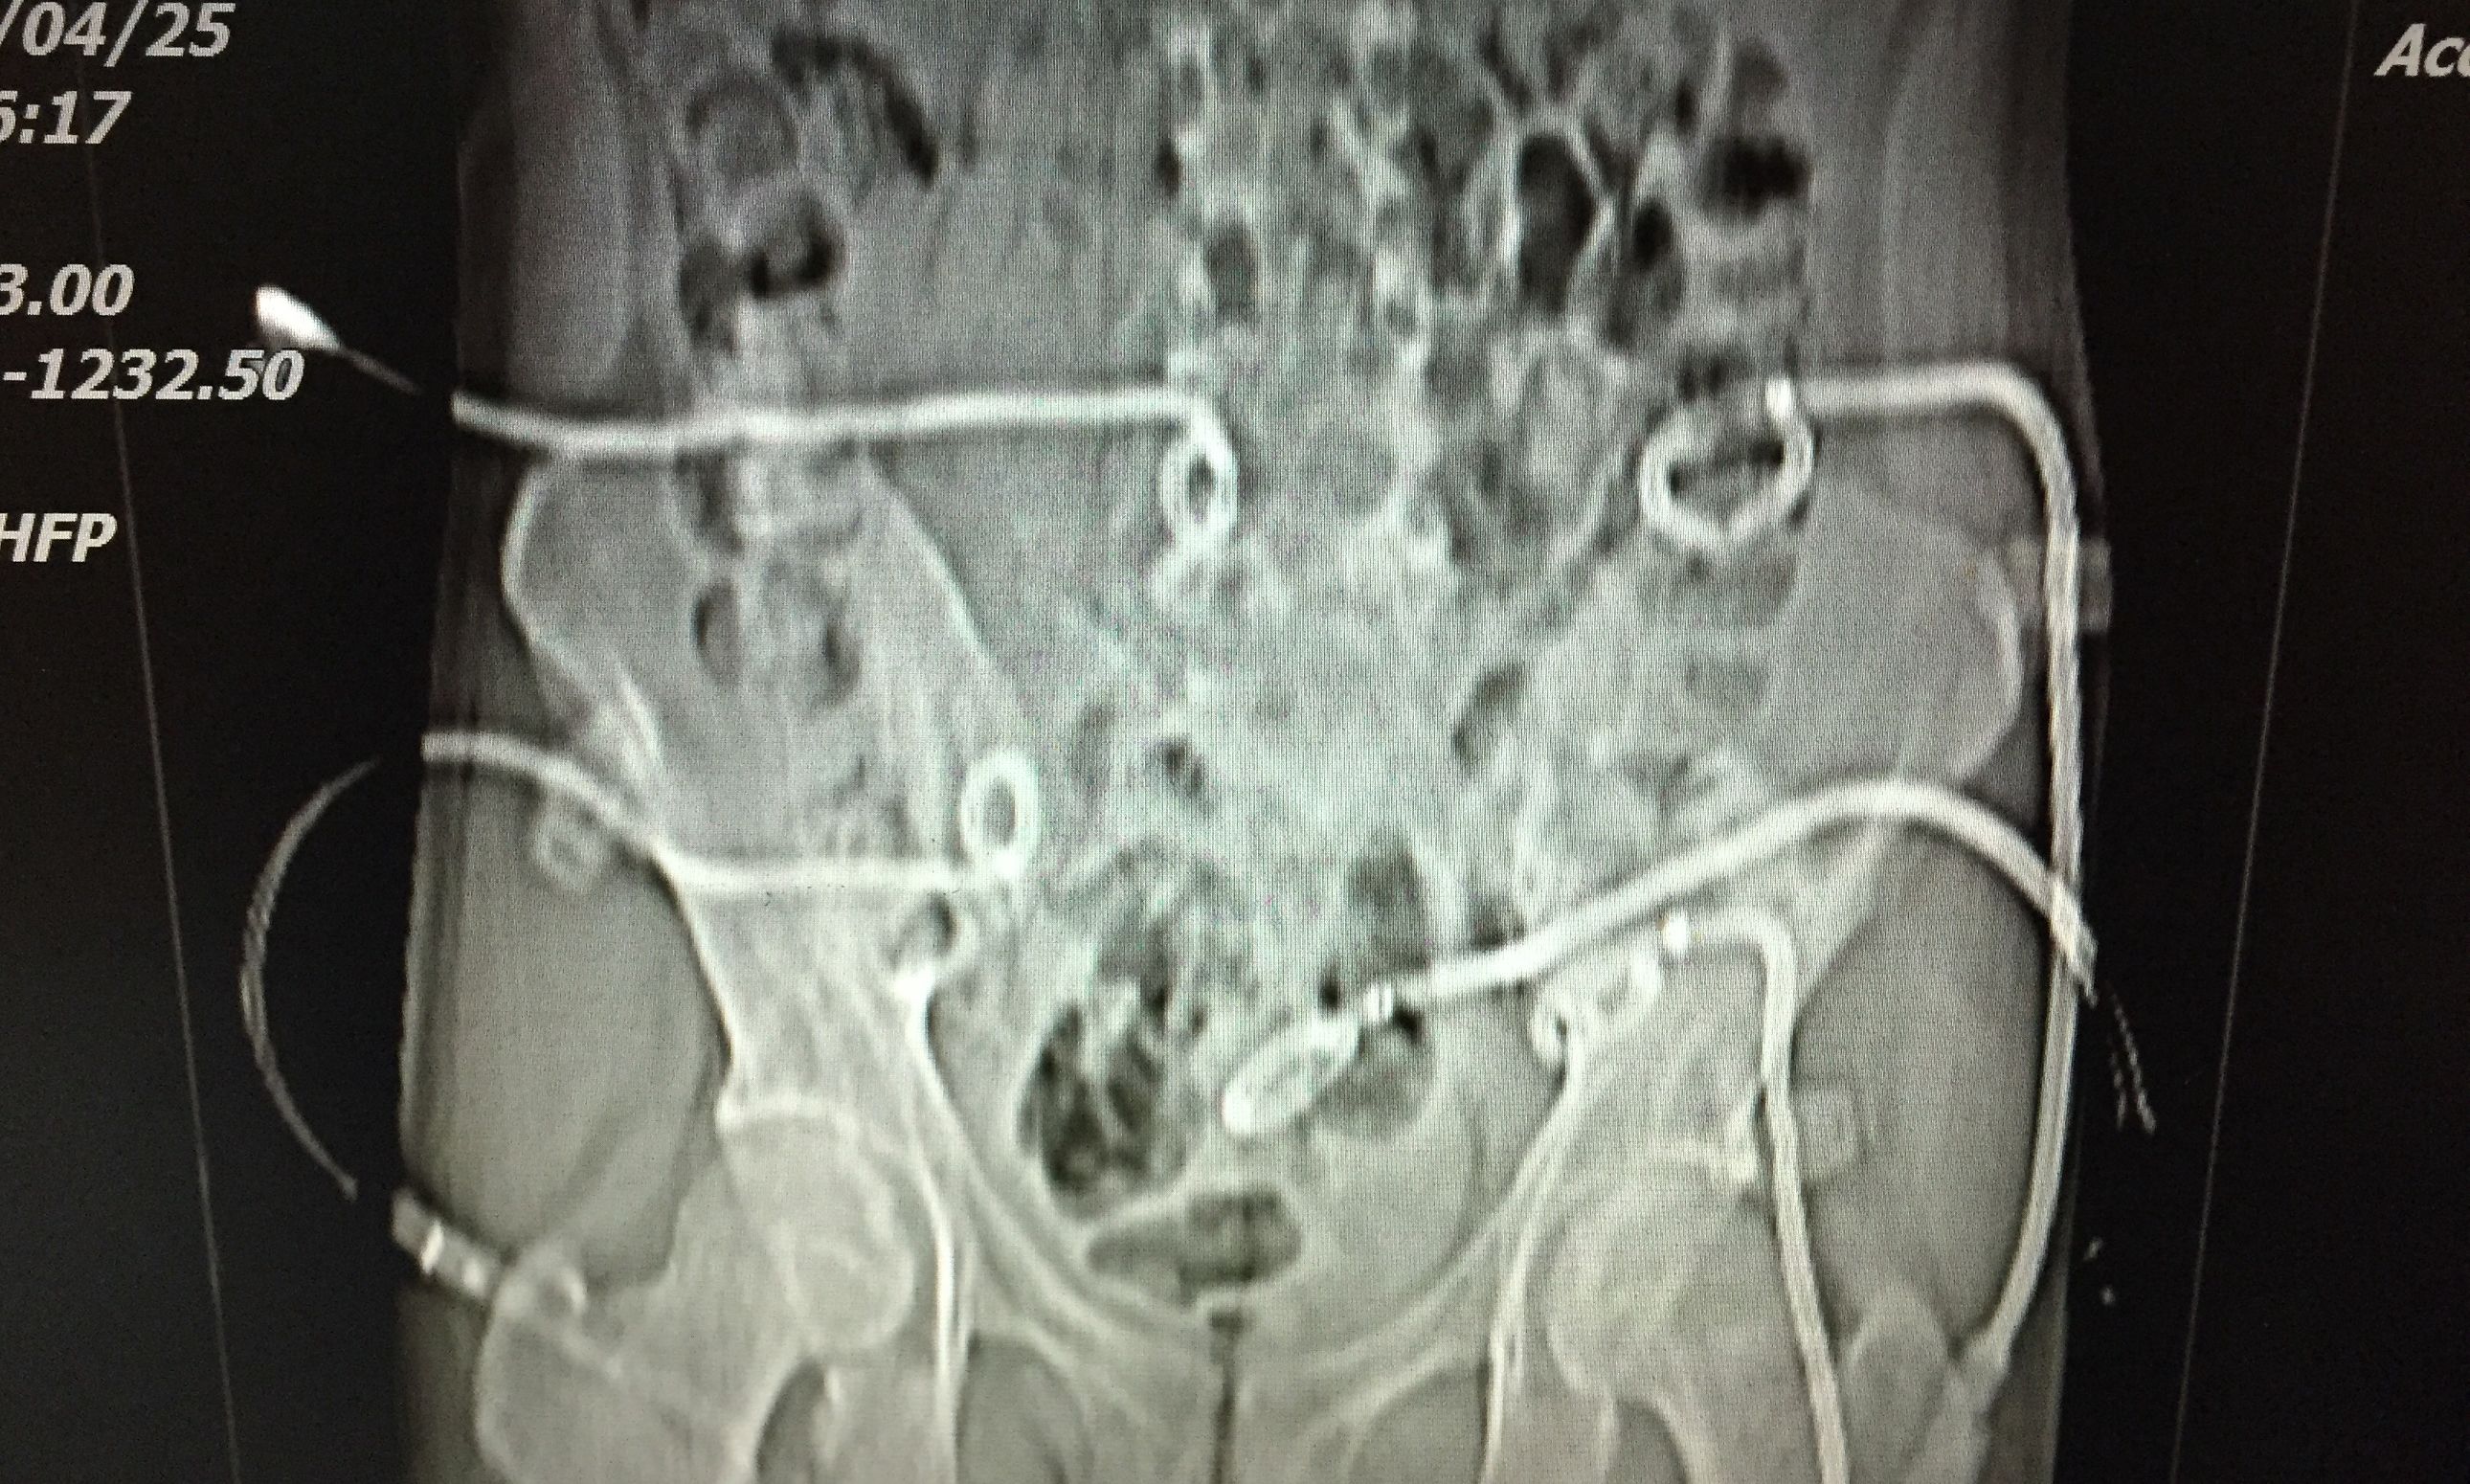

我们对患者在门诊进行充份置管引流(白色条状物5根)

在患者持续引流态势下,并联合抗痨治疗。如下图所示,脓肿完全吸收。患者痊愈。